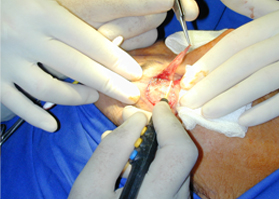

適用于細(xì)微、精細(xì)的切割如頭頸部,敏感部位皮膚的切割。

可實(shí)現(xiàn)切割,凝血同步。

適合于皮下組織的切割和剝離。

特別是在運(yùn)血較為豐富的部位。